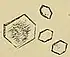

| Calcium oxalate | 60% | when urine is acidic (decreased pH)[70] | Black/dark brown ![]() |

Radio-opaque | Some of the oxalate in urine is produced by the body. Calcium and oxalate in the diet play a part but are not the only factors that affect the formation of calcium oxalate stones. Dietary oxalate is found in many vegetables, fruits, and nuts. Calcium from bone may also play a role in kidney stone formation. |

Calcium oxalate crystals can come in two varieties. Calcium oxalate monohydrate can appear as 'dumbbells' or as long ovals that resemble the individual posts in a picket fence. Calcium oxalate dihydrate have a tetragonal “envelope” appearance.[74]

Uric acid stones appear as pleomorphic crystals, usually diamond-shaped. They may also look like squares or rods which are polarizable.[74]